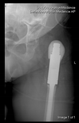

The direction of the cup stem was determined by the guide wire. The aiming device was needed to introduce this wire. After removing the aiming device, the next step was the drilling. Since a cannulated drill bit was used, the previously installed wire could guide the process. A self-positioning reaming tool was then used in the drilled channel. In the prepared cavity, the cup was fitted perfectly. Of the two stemmed cups available to us, the McMinn cup (Waldemar Link, Hamburg, Germany) had the simpler geometry and was therefore chosen. The stemmed cup was inserted according to the manufacturer’s recommendation. In the presence of a significant bone defect, a synthetic bone graft may be impacted for substitution.

The radiological examination allowed us to verify the close bone-to-implant contact and the unchanged position of the implant during follow-up.

In all the cases operated with the above-described targeting procedure, the stems of the cups remained between the cortical bone surfaces without perforation of the linea terminalis, as shown by postoperative radiographs. There were no complicated surgical situations. In 16 cases, the wound healings were uneventful, and the hips were able to bear weight again after postoperative rehabilitation.